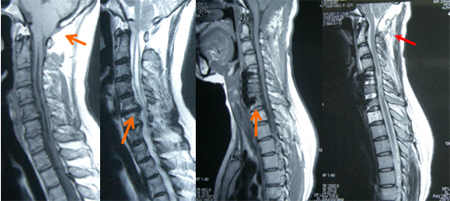

Chiari 畸形伴发脊髓型颈椎病(颈前、后路手术)

女性,35岁,双上肢麻木无力5年,加重3月,伴走路不稳。查体:Romberg征(+),双上肢片状针刺痛觉减退,双上肢近端肌力4级,远端3级,双手指伸直困难,稍嫌爪形手畸形,双侧Hoffman征(+)。术前图片:小脑扁桃体疝入椎管内,枕大孔平面下5mm多、颈5-6,6-7间盘突出、脊髓空洞形成;行颈前路颈5-6,6-7间盘摘除、髂骨取骨植骨、钛板内固定和颈后路枕颈减压、枕大池成型术;术后图片示:脊髓腹侧受压减除,椎管空间扩大,颅颈交界骨性、软性空间都获扩大,脊髓空洞消失。

专家评点:患者的临床表现和体征不能完全肯定仅限于寰枕畸形或颈椎病之一所致、或言之症状和体征不能明确和另外一种病变完全无关,为了避免二次全麻下手术的痛苦和经济负担,所有患者均行一期手术解决病变所造成的延颈髓压迫或变形。颈前路手术适应症:1~2个节段的椎间盘突出或骨赘所致脊髓腹侧受压者,孤立型颈椎后纵韧带骨化(OPLL),局限性椎管狭窄,节段性不稳定者。